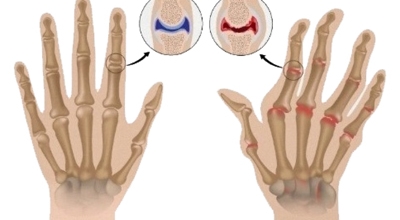

관절염은 관절 연골이 파괴되고 관절에 염증성 변화가 일어나는 질환을 의미한다고 하며 관절은 두 개 및 그 이상의 뼈들이 맞닿는 곳을 말한다고 합니다. 관절을 이루는 뼈들의 끝은 연골이라 하는 부드러운 재질로 싸여 있으며 연골은 쿠션처럼 관절이 쉽게 움직이도록 도와 준다고 해요. 그리고 활막이라고 하는 섬유질 막으로 싸여 있고, 마찰을 막아주는 활액을 분비해 주어요.

골관절염(및 퇴행성 관절염)은 손목, 엄지손가락 기저부에 위치한 관절, 손가락의 중간 또는 상부 관절에 영향을 미쳐요. 골관절염이 있다면 연골이 마모되어 결과적으로 뼈가 서로 마찰되어 손상돼요. 연골과 뼈의 이런 점진적 마모는 경직, 기형 또는 통증을 일으킬 수 있어요.

류머티즘 관절염은 인체의 자연 면역계가 자신의 건강한 조직을 공격하기 시작해서 관절 내막에 염증을 유발하는 자가면역 질환이지요. 이로 인해 연골이 파괴되어 결과적으로 뼈가 부식돼요. 이 만성 상태는 손목, 손, 손가락의 작은 관절에 대칭적으로 영향을 미쳐요.

류마티스관절염은 면역질환의 하나로 관절이 부으며 통증이 생기며 변형이 되는 질병이라고 합니다. 퇴행성 관절염과는 원인이 다르고 증상에 있어서도 차이가 분명히 있어요. 퇴행성은 무리하여 사용해서 통증이 발생을 할 경우 류마티스는 휴식 후 악화가 되는 특징이 있다고 합니다.